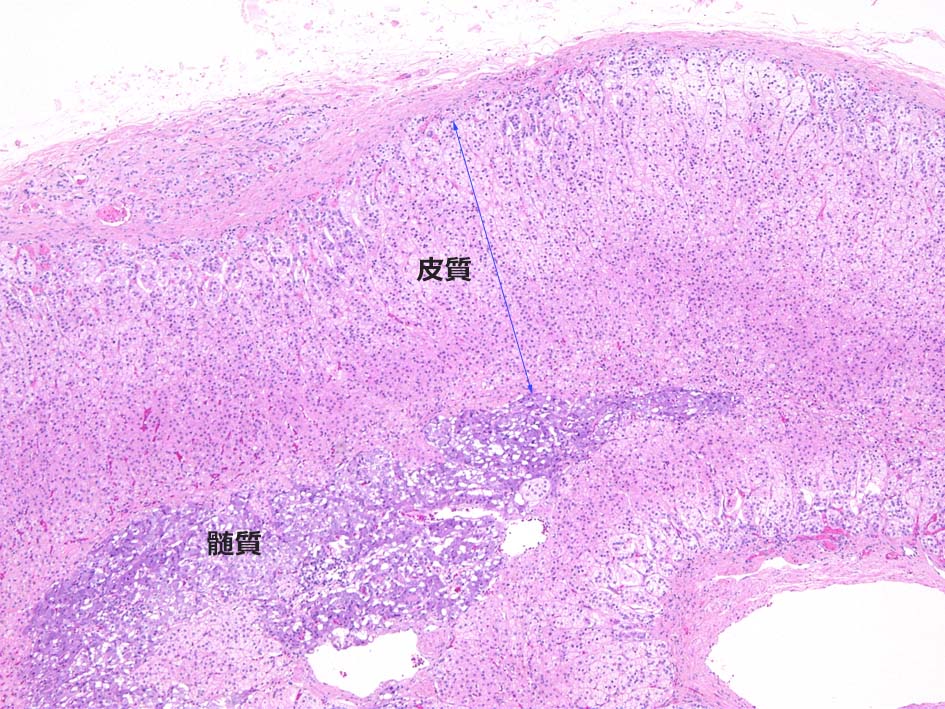

副腎は細胞成分に乏しい線維性被膜に被覆される. 被膜下には皮質の層構造が認められ中心部には交感神経由来細胞が集簇し髄質を形成している.

皮質には境界の不明瞭な3層構造が認められる. 被膜直下より, 球状層(Zona Glomerulosa), 束状層(Zona Fasciculata), 網状層(Zona Reticularis)と呼ばれ各々性状, 形態の異なる細胞より構成されている.

球状層(ZG):

球状層細胞は境界明瞭な細胞で少量の線維血管性間質で囲繞された小型クラスターを形成している. クラスターはときに集簇して短い柱状, 直線状, 曲線状, あるいはヘアピン様の形状をしめすことがある.

淡い好酸性, amorphous(無構造)な細胞質でわずかに空胞状を呈する. 核は卵形で他の皮質層細胞と区別は困難であるが, より小型でクロマチンに濃染する.

束状層(ZF):

皮質の1/2を占め幅が最も広い層. ZG, ZRとの移行は形態的に不明瞭. 束状層細胞は大型で, 円形核と豊富な細胞質をもつ. 細胞2個分の幅を有する長い柱状構造を示す.

核は球状層細胞に比べよりvesicularで, クロマチンは淡い. 外側2/3細胞の細胞質は脂肪を豊富に含むため泡沫状, スポンジ様の淡明な所見を示す.

網状層(ZR):

網状層は副腎尾側部では通常欠損している. 網状層細胞は皮質の1/4程度の厚さを占め, スポンジ様の網目構造を形成し周囲には拡張した血管が存在する.

網状層細胞は境界明瞭な細胞で, 束状層細胞より小型であり, 顆粒状, 好酸性の細胞質をもち, 脂肪含有量は少ない. 髄質近傍の網状細胞はリポフスチンを含むため黄褐色を呈する.